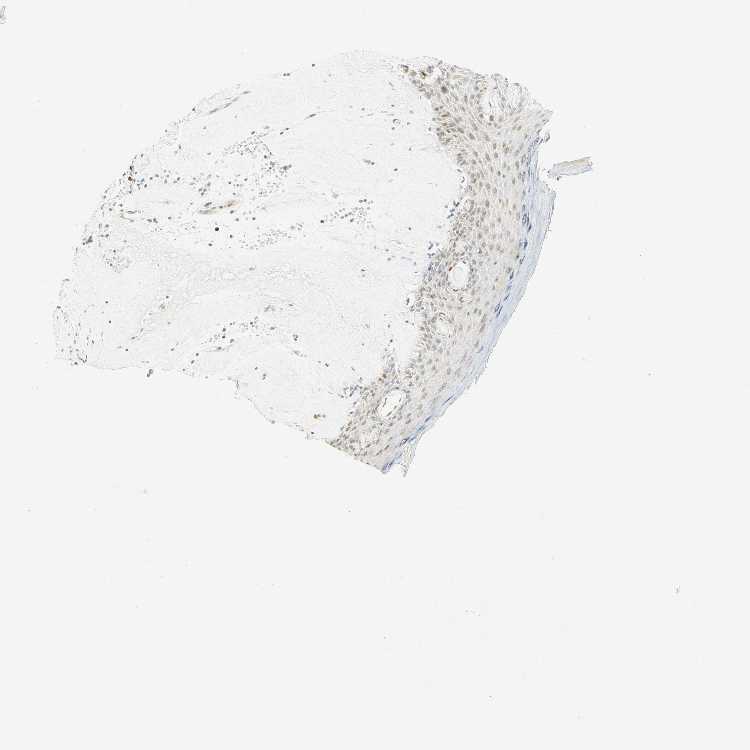

SKIN 1 - Antibody stainingi

Antibody staining in the annotated cell types in the current human tissue is reported as not detected, low, medium, or high, based on conventional immunohistochemistry profiling in selected tissues. This score is based on the combination of the staining intensity and fraction of stained cells.

Each image is clickable and will lead to virtual microscopy that enables deeper exploration of all samples and also displays staining intensity scores, fraction scores and subcellular localization as well as patient and tissue information for each sample.

Antibody HPA008003Antibody CAB000329Antibody CAB019308

Langerhans MediumNot detectedHigh

Fibroblasts HighMediumMedium

Keratinocytes LowMediumHigh